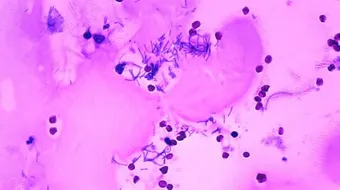

يحدث التهاب السحايا عادة بسبب الإصابة بعدوى فيروسيّة، وقد يكون السبب هو الإصابة بعدوى بكتيريّة أيضاً، كما يمكن أن تُسبِّب العدوى الجرثوميّة غير الشائعة التهاب السحايا، وفيما يأتي بعض أنواع، وأسباب الإصابة بالتهاب السحايا:[2]

- التهاب السحايا البكتيريّ: هناك العديد من أنواع البكتيريا المُسبِّبة للإصابة بالتهاب السحايا البكتيريّ، ومنها:

- النيسيريّة السحائيّة (بالإنجليزيّة: Neisseria meningitidis)، وعادةً ما تُسبِّب هذه البكتيريا عدوى الجهاز التنفُّسي العُلويّ.

- البكتيريا المكوَّرة الرئويّة (بالإنجليزيّة: Streptococcus pneumoniae)، حيث تُعَدُّ هذه البكتيريا السبب الأكثر شيوعاً للإصابة بالتهاب السحايا البكتيريّ عند الرُّضَّع، والأطفال.